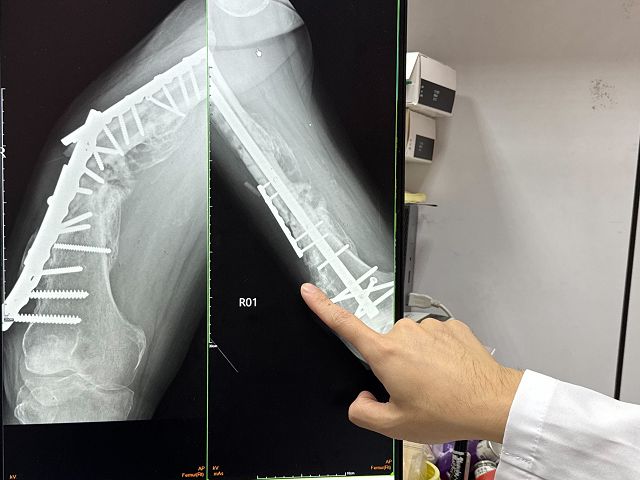

駐診在大甲李綜合醫院的臺中榮總骨科主治醫師廖唯任表示,該患者當初大腿骨折斷成三截,手術治療後,卻因體重、血液循環不好,再加上「大腿骨是全身上下最難愈合的部位」,導致內固定失敗,植入物斷裂骨不癒合,讓患者不良於行無法正常走路。

廖唯任說,患者裝在大腿內的鋼板後來因金屬疲勞等多種因素斷裂,只能靠著輪椅代步,因此,決定再手術。手術時,把壞死的骨頭移除,把大腿內舊有斷掉的鋼板、鋼釘全部拆除,讓骨頭「再次活化」,改用髓內鋼釘固定,使得骨頭有機會再次癒合,術後能立刻下床負重,恢復日常行走功能。